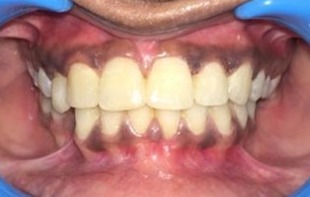

PRE - OP POST - OP